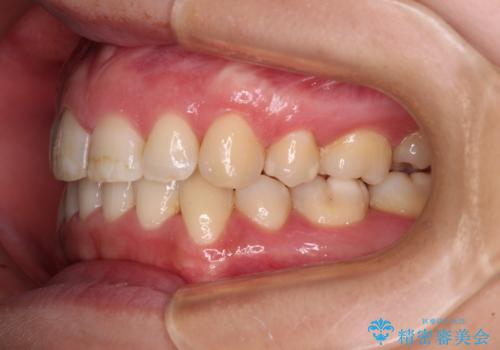

前歯のデコボコを短期間で解消 ワイヤー装置による抜歯矯正

当初予定は2年半程度と伝えていましたが、2年にも満たない期間で治療を終えることができました。